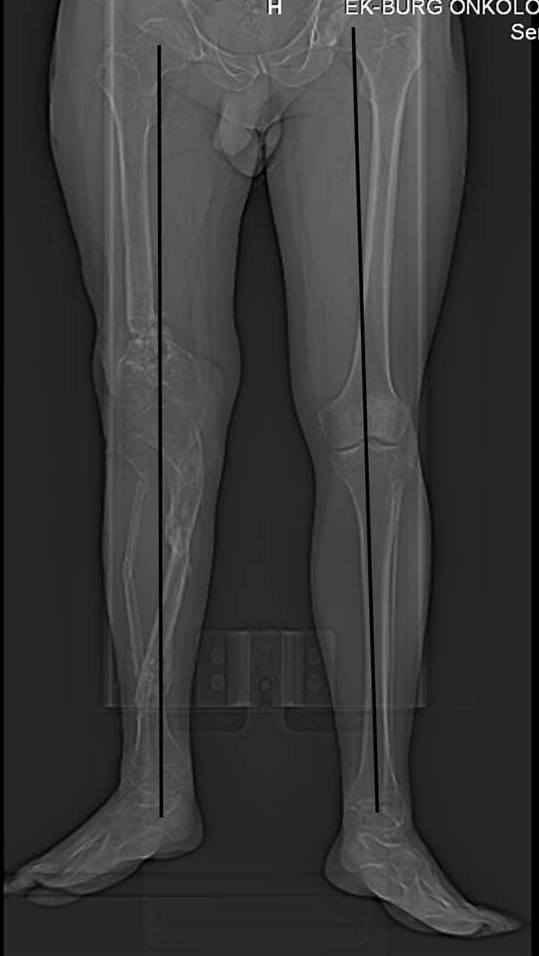

Относительное укорочение - 6,1 см по КТ, осевую реконструкцию прилагаю (возможно не совсем

Имя     : ось.jpg